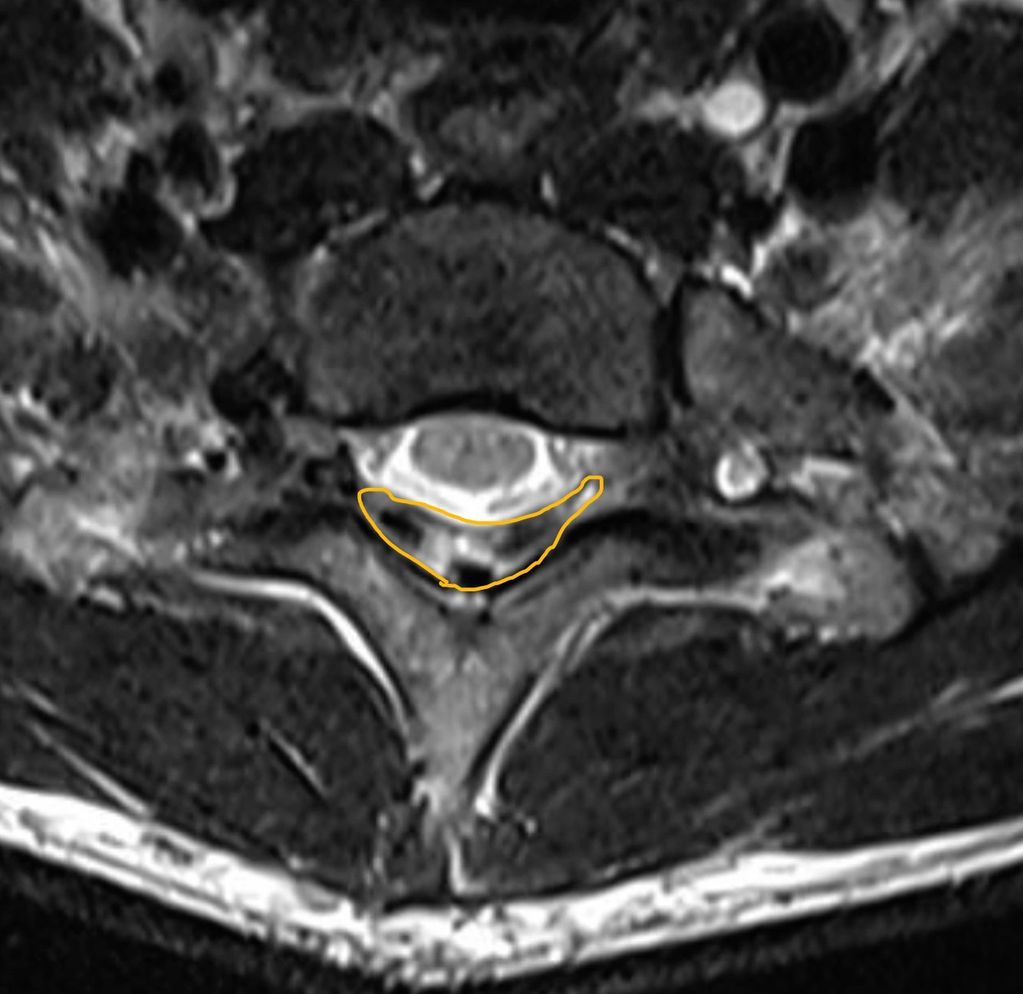

Neutral position: Axial T2 MRI of cervical spine showing right hemicord signal changes

Flexion MRI: Axial T2 weighted image of cervical spine showing posterior dural laxity/increase in laminodural space flattening of the cord